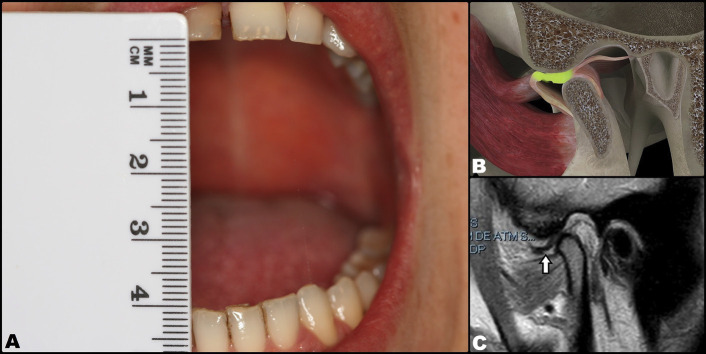

Arthrocentesis (joint lavage and lysis) and hydraulic distension of the temporomandibular joint have been described as effective options for reducing joint pain and improving function in patients with limited mouth opening (closed lock) due to disc displacement without reduction, fundamentally in the acute phase of the disorder. Despite controversy, some studies suggest that in addition to improving the range of opening and reducing joint pain, the disc can also be reduced in some cases. The present study was carried out to determine whether arthrocentesis could reduce the displaced disc in a woman with 6 weeks of closed lock, and to assess its efficacy in improving mouth opening and reducing joint pain. Key words:Arthrocentesis, closed lock, disc displacement, limited mouth opening, disc reduction, disc recapture.